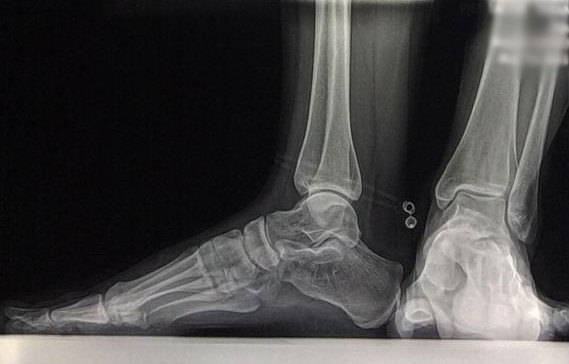

Cambios Térmicos en las Extremidades de Caballos,

Asociados a Golpes y su Evaluación por Termografía.

Los caballos de salto, en competencia, pueden derribar obstáculos y lastimarse. Si se golpean, no siempre claudican. Considerando al calor como un signo de inflamación, se evaluaron los cambios térmicos de 6 áreas de las extremidades torácicas y pelvianas de 23 caballos de salto en nivel de competencia de 1.05 a 1.60 m de altura, por medio de termografía durante 4 días de competencia (N=2208 áreas).